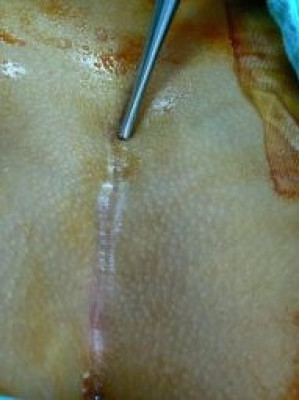

Reseccioón quiste pilonidal

Envíado por Dr. Carlos Miguel Zavaleta Consuegra